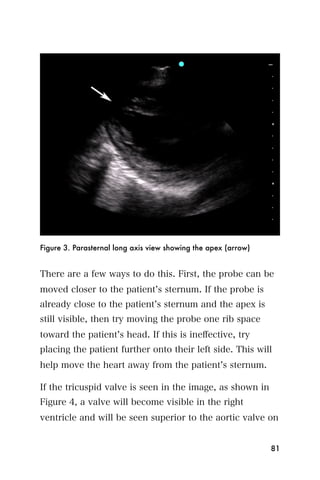

Figure 3. Parasternal long axis view showing the apex (arrow)

There are a few ways to do this. First, the probe can be

moved closer to the patient s sternum. If the probe is

already close to the patient s sternum and the apex is

still visible, then try moving the probe one rib space

toward the patient s head. If this is ineffective, try

placing the patient further onto their left side. This will

help move the heart away from the patient s sternum.

If the tricuspid valve is seen in the image, as shown in

Figure 4, a valve will become visible in the right

ventricle and will be seen superior to the aortic valve on

81

the screen. The probe should be tilted up towards the

patient s head slightly.